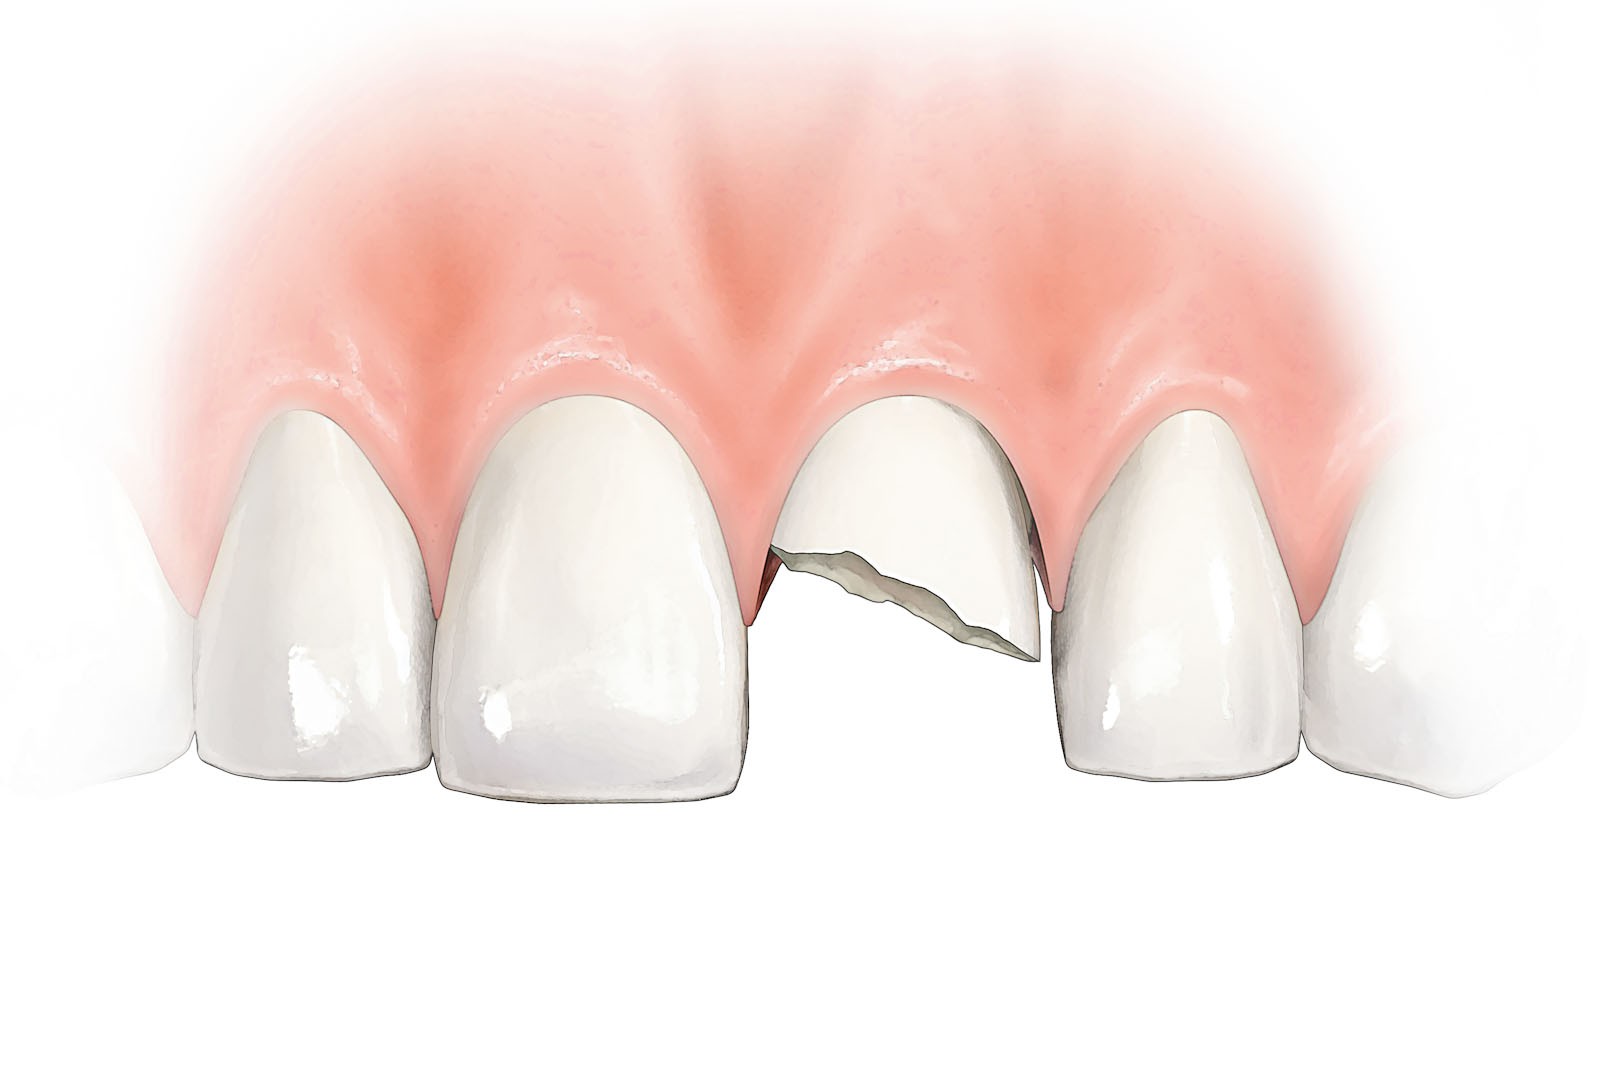

- Chirurgiczne zaopatrzenie urazów zębów